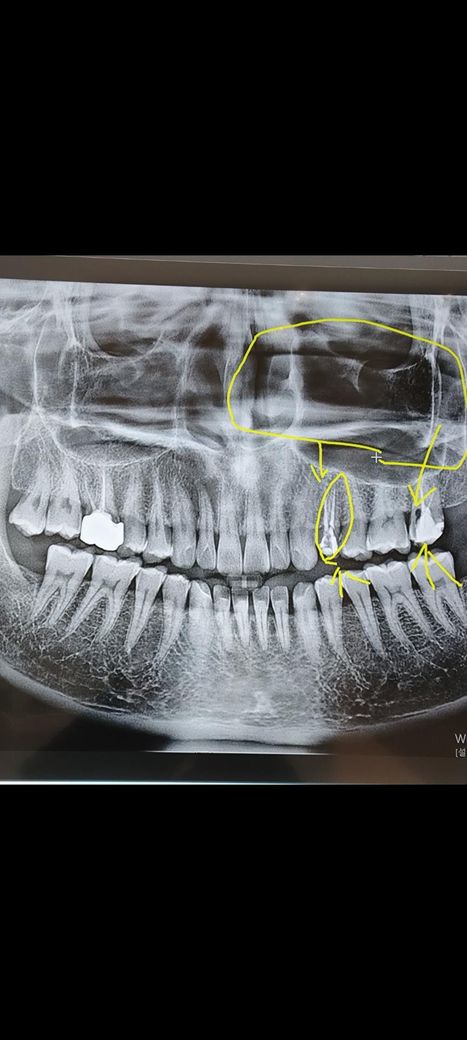

xray 사진 보시구 치아성 상악동염이 있는지 확인부탁드려요

엑스레이 사진상 오른쪽 위작은어금니가 급성치수염이후

신경치료를 여러차레 받았으나 머리가 지근거리고 전기가흐르는 느낌

왼쪽코 눈밑이 무거운 증상 이상감각이 게속되고 있어서

발치를 고민중인 1인인데요 세균이나 염증이 뇌까지 간거

엑스레이사진상으로 오른쪽 윗어금니인데 사진보시고

상악동 부비동에 이상이 있는지 판별해주시면

정말정말 감사드립니다.

부비동염은 없을 것 같은데요. 치과 치료를 일단 잘 받으시고, 세균이 뇌로 가는 경우는 거의 없으니 염려하지 마시길 바랍니다. 만약 발치 이후에도 계속 아프다면 신경과에서 진료를 받아보시는 것을 권유드립니다.